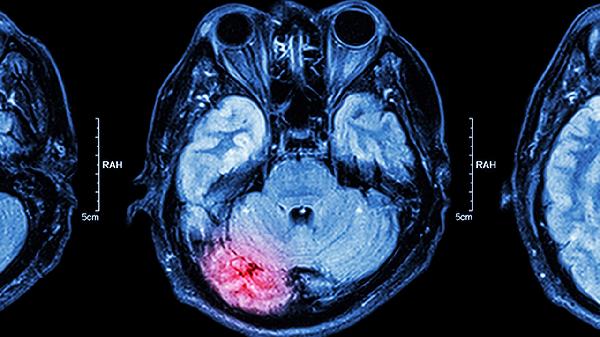

孩子颅内感染需根据病原体类型采取抗感染治疗,主要方法有抗生素治疗、抗病毒治疗、降颅压治疗、糖皮质激素治疗、免疫调节治疗。需立即就医,避免自行用药。

颅内压增高患儿需使用甘露醇、高渗盐水等脱水剂,严重者可考虑脑室引流。需密切监测瞳孔变化和意识状态,维持水电解质平衡。床头抬高30度有助于静脉回流,控制液体入量在每日生理需要量的70%-80%。

重症患儿可静脉注射免疫球蛋白,对自身免疫性脑炎需采用血浆置换或利妥昔单抗。部分特殊感染如隐球菌性脑膜炎需联合两性霉素B和氟胞嘧啶。治疗期间需定期复查脑脊液和影像学。